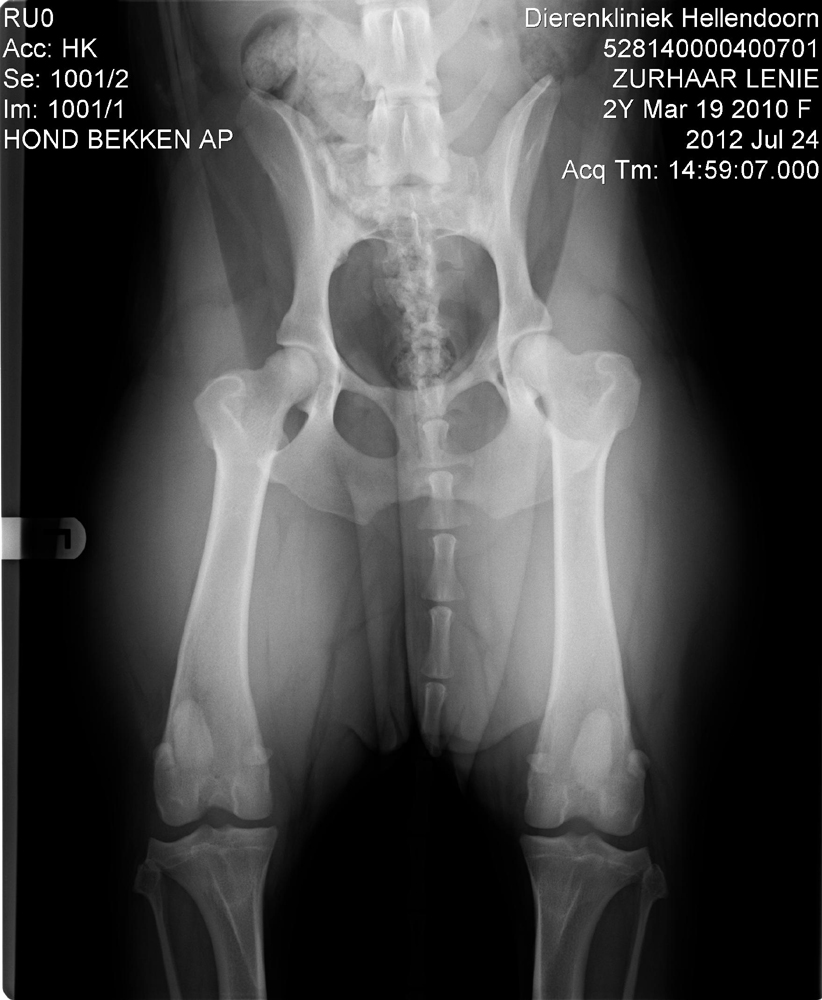

Hüfte

.

(Beide Bilder könnt Ihr anklicken um sie Euch vergrössert anzeigen zu lassen.)

Die Hüfte hat der Doc mir, wenn wir die Bilder hätten auswerten lassen wollen, mit HD 0 eingeschätzt. Bei den Ellenbogen handelt es sich nach seiner Meinung leider um eine ED 1....